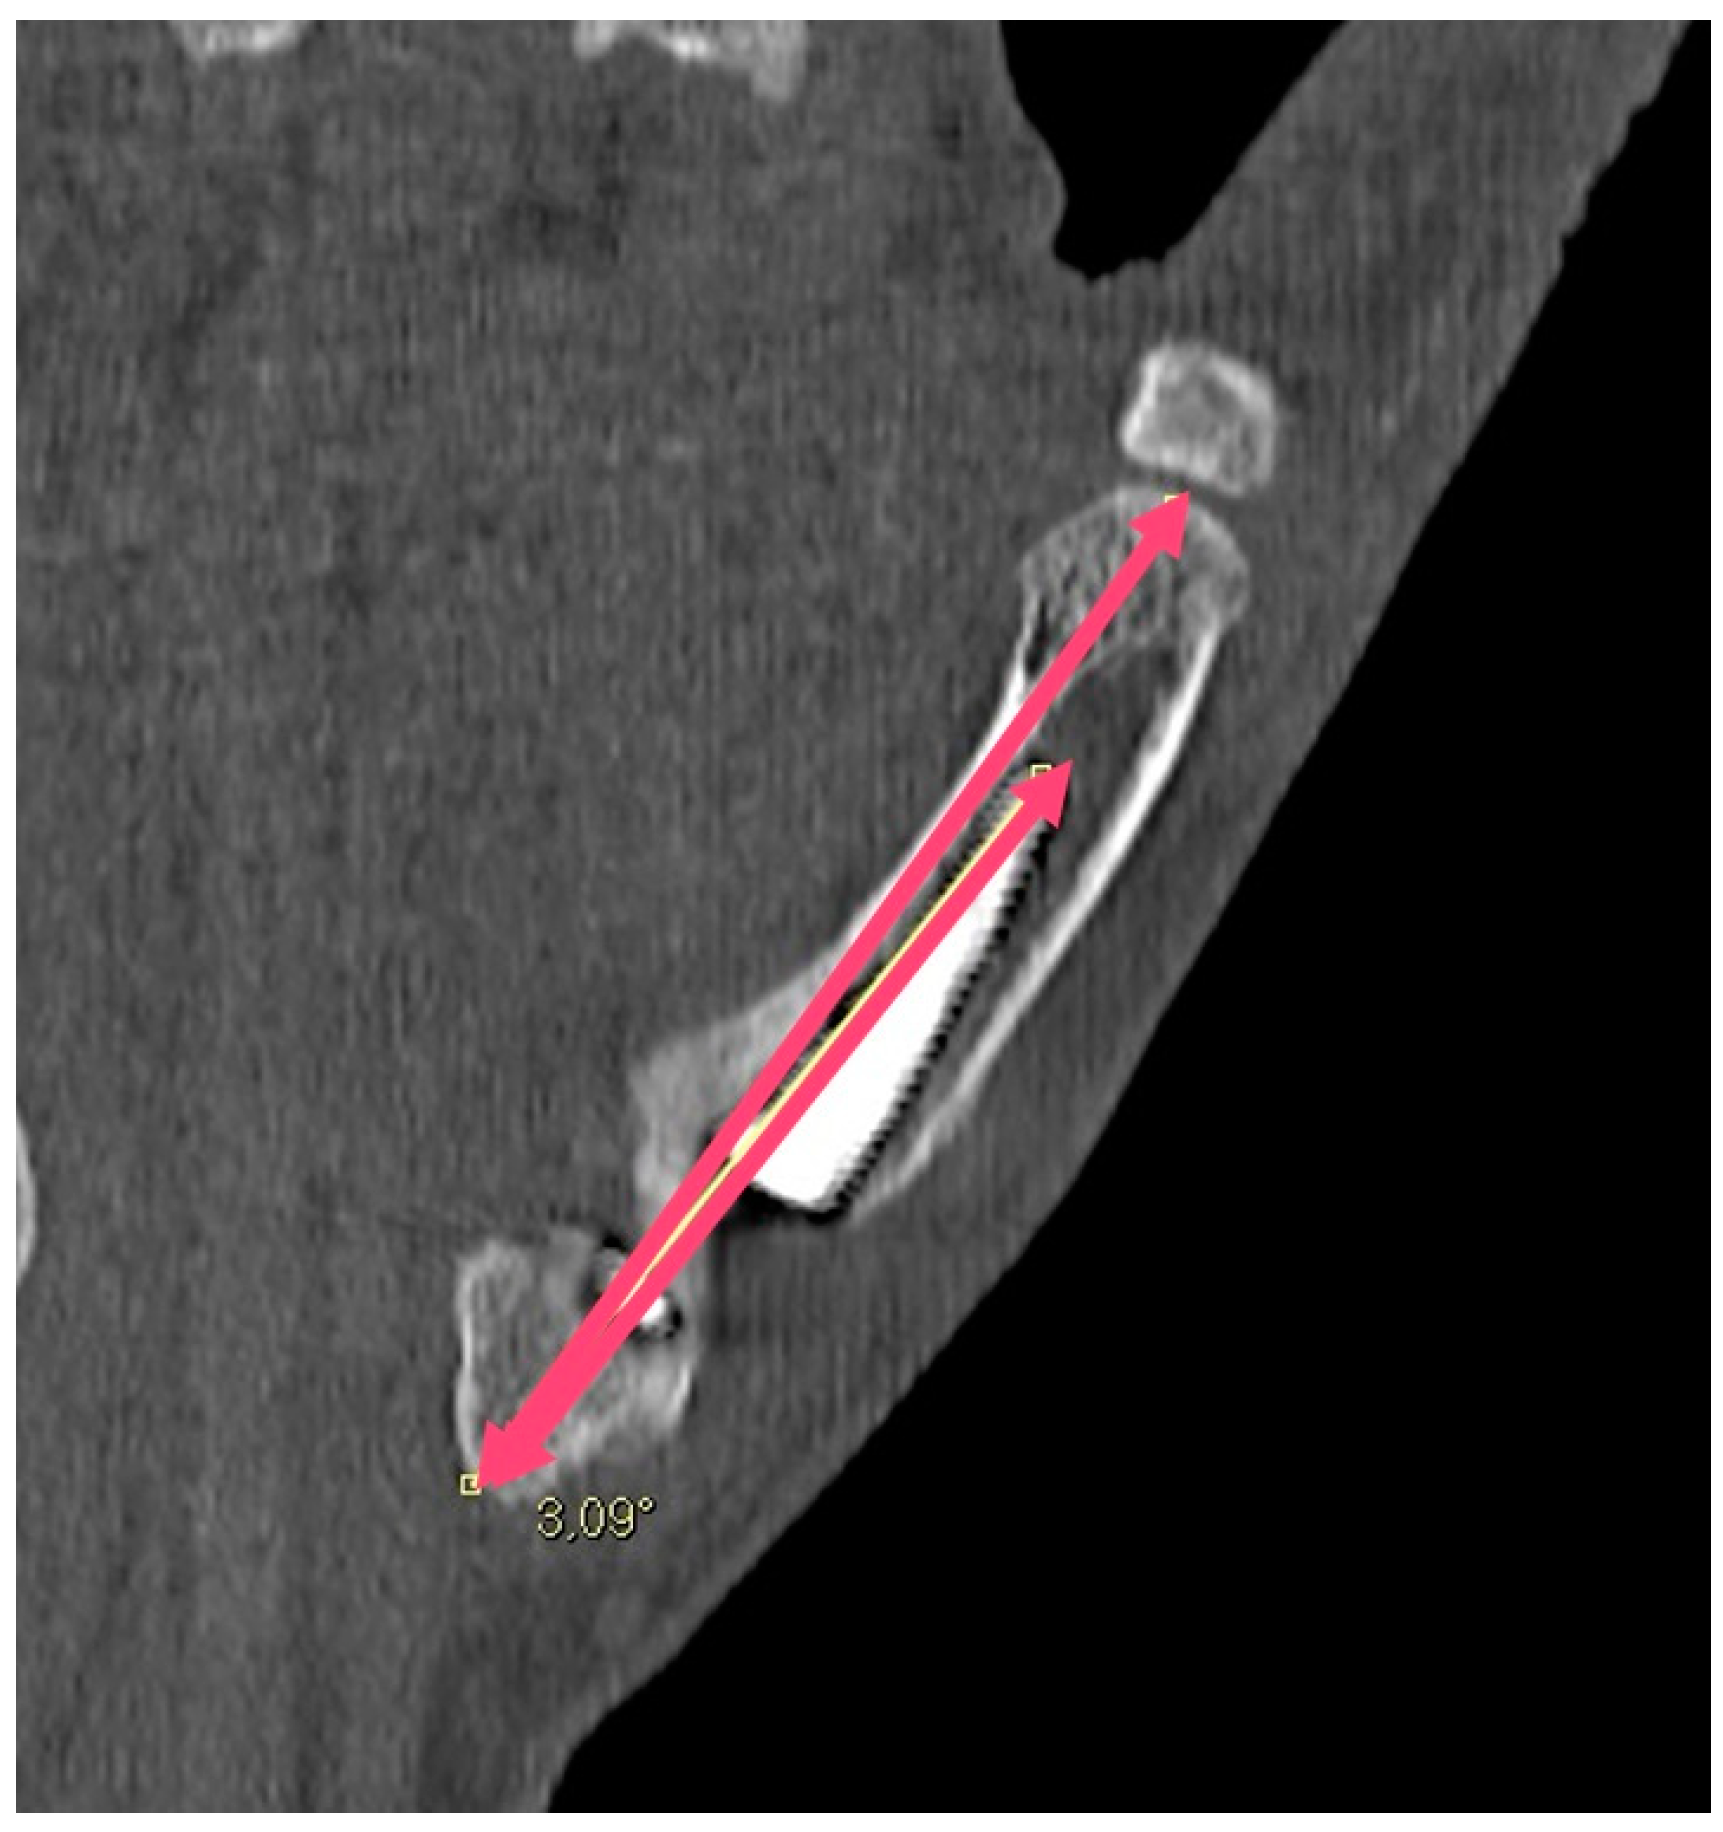

| Angle between the prosthesis axis and the M1 axis | 2.8° | ±1.3° |